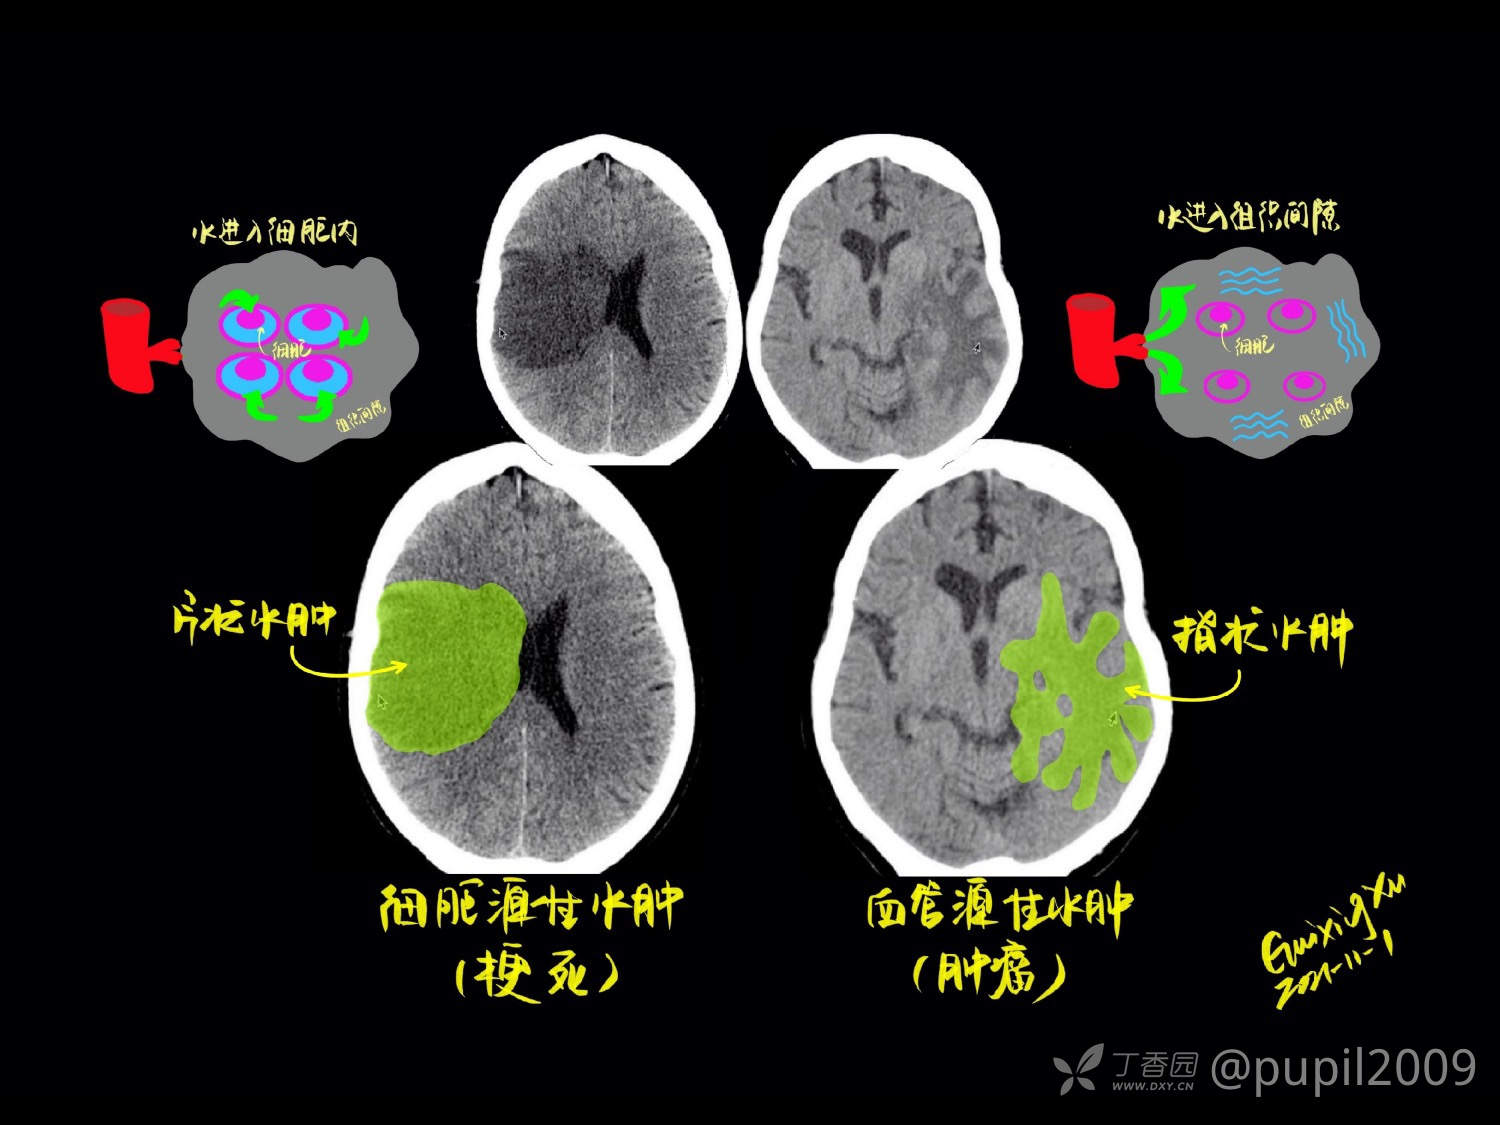

头颅连续断层解剖是通过逐层分析不同平面影像,研究颅骨、脑组织及血管等结构的空间关系,为医学影像诊断和神经外科手术提供精准定位依据。核心在于理解冠状、矢状、水平三个标准切面下的解剖层次,需结合CT、MRI等影像技术掌握关键结构的形态特征。对于医学学习和临床工作,理解头部CT断层解剖是解读影像、诊断疾病的基础。它是影像诊断从“看图”上升到“识病”的必备桥梁。